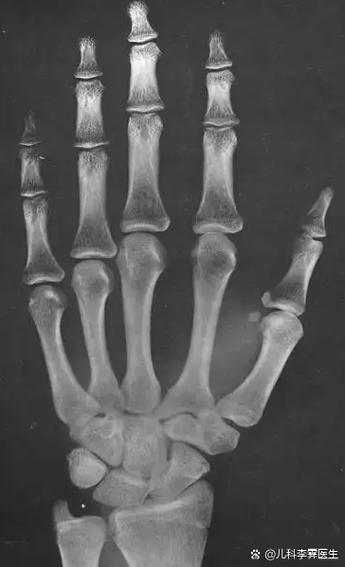

试管婴儿技术对骨龄的影响:是否会变小?

我想知道做了试管婴儿技术之后,孩子的骨龄是不是会有变小的情况呀?是所有做试管婴儿出生的孩子骨龄都会变小,还是只是部分会这样呢?这种骨龄变小的情况对孩子的生长发育会有什么具体影响吗?有什么办法可以避免或者改善如果出现骨龄变小的状况呢?